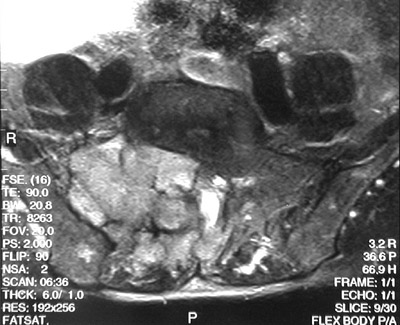

The large destructive mass seen here with oblique T1 weighted MRI scan above and T2 weighted scan below is a chordoma. It is arising in the sacrum and extending to the right.